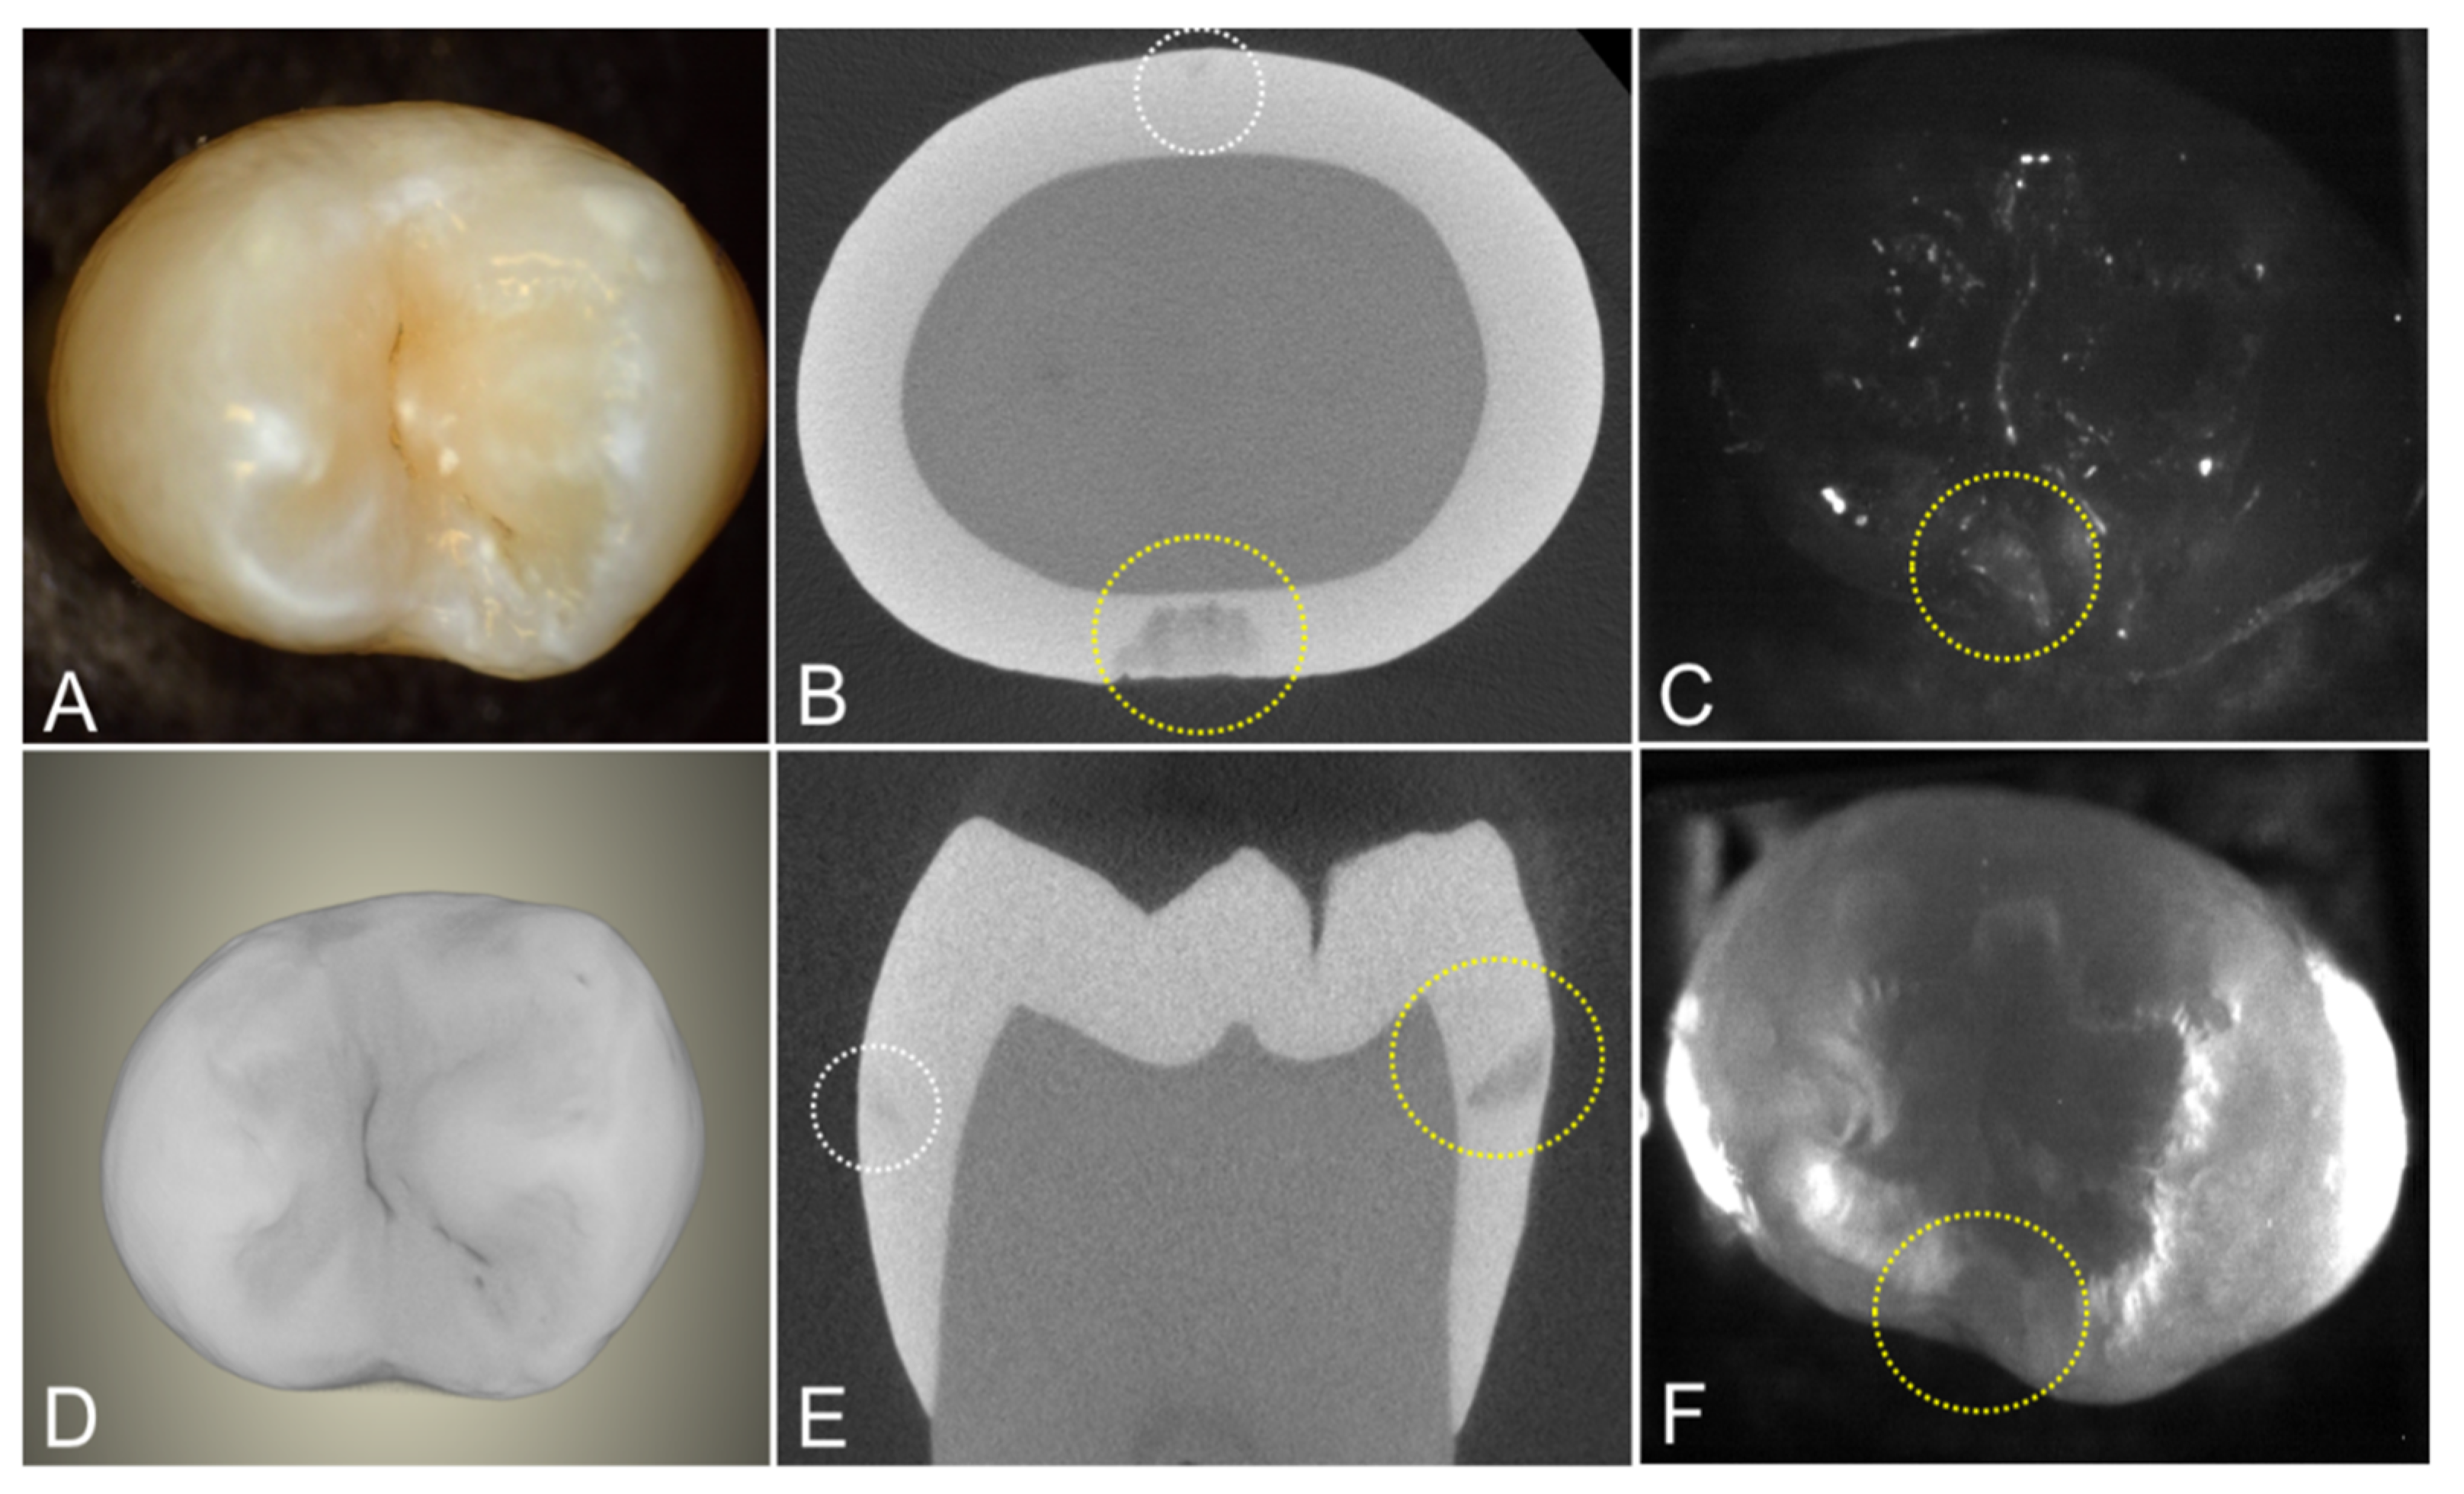

Another tooth with two interproximal lesions is shown in Figure 4. One lesion penetrates almost to the dentin in the microCT image. The other lesion is very small and is barely visible in the microCT images. Occlusal transillumination and occlusal reflectance images are shown, and the larger lesion is visible in both the transillumination and reflectance images.

Figure 4. Images of a tooth with two interproximal lesions, one that is quite small and is only visible in the microCT images (white circle) and one much larger that was also visible in the SWIR images (yellow circle). (A) color and SWIR (C) occlusal reflectance and (F) occlusal transillumination are shown along with a (D) microCT surface rendering of the tooth and extracted slices (B) transverse and parallel. (E) to the long axis of the tooth.